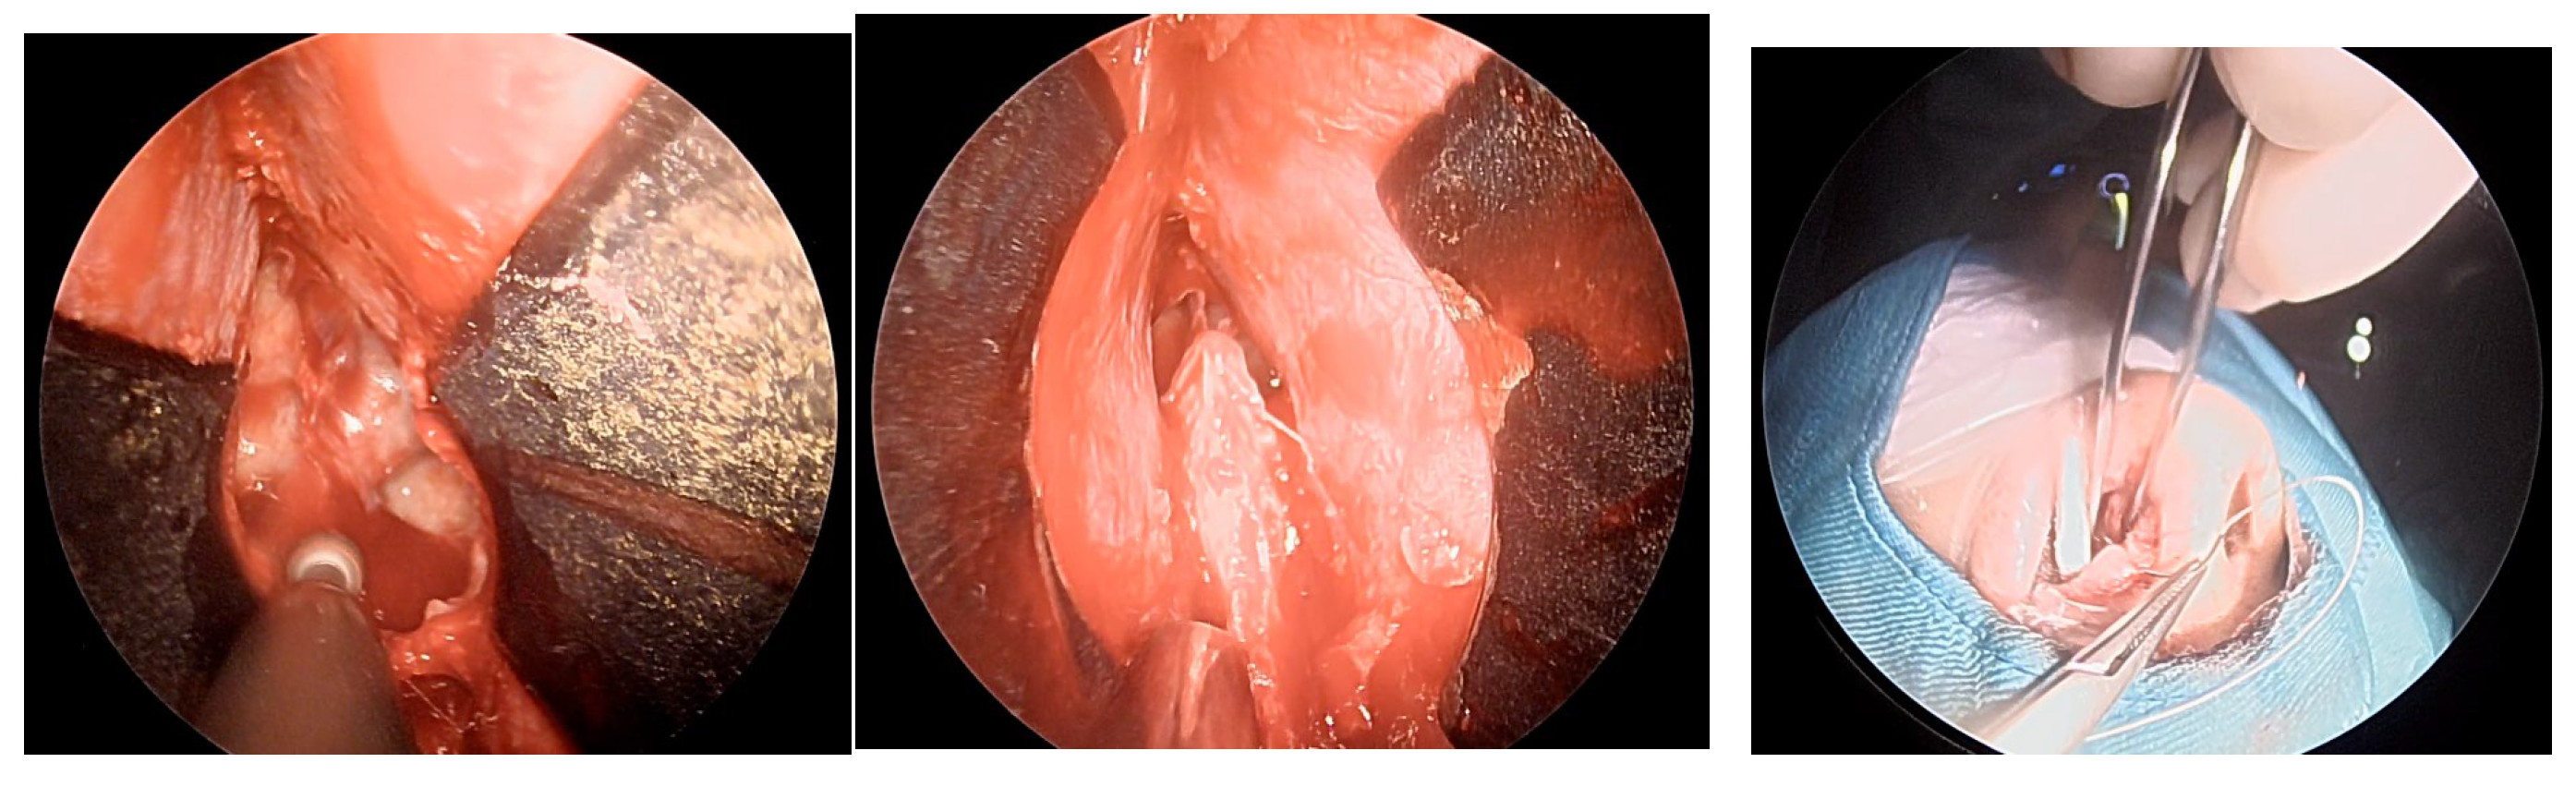

Once the mucosal dissection is completed, self-retaining nasal speculum is placed between the mucosal flap and the cartilaginous nasal septum obtaining sphenoidal exposure (Figure 3).

After removal of the adenoma and placement of autologous adipose tissue, as shown in Figure 4 unilateral mucosal reconstruction is performed by placing a simple interrupted suture thought mucosal flap and cartilaginous septum.

The patient underwent endoscopic ENT follow-up 4 days after the operation and 30 days later (Figure 6).

Figure 3. positioning of self-retraining nasal speculum between nasal septum and mucosal flap and drilling of the sphenoid bone.

Figure 4. placement of simple interrupted suture.

Figure 6. ENT 4 days after surgery and 30 days later.